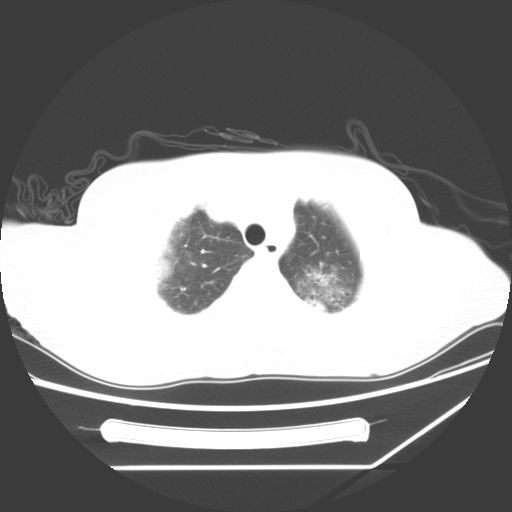

标题: CT25393:病人45岁,咳嗽,吐黄痰带血丝,发热,胸闷月余 [打印本页]

1、左肺中央型肺癌并双肺弥漫性转移   2、双肺部感染    3、肺大泡     4、左侧胸腔积液

双侧肺弥漫性病变,可见“空泡征”及“蜂窝征”,考虑肺泡癌可能性大,左侧胸腔积液,考虑胸膜受累可能!

考虑肺泡癌,建议排除感染。

考虑肺泡癌

1)不排除肺泡癌可能。2)左侧胸腔积液。